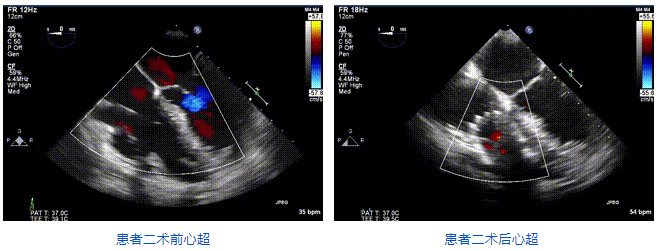

2021年12月24日,復(fù)旦大學(xué)附屬中山醫(yī)院葛均波院士團(tuán)隊(duì)成功應(yīng)用LuX-Valve Plus為一例極重度三尖瓣反流(TR)合并房顫、房缺的患者完成了經(jīng)血管三尖瓣置換術(shù),這是在前基礎(chǔ)上,本周完成的第三例經(jīng)血管三尖瓣置換手術(shù),葛均波院士、周達(dá)新教授等與心外科魏來教授、賴顥教授,心超室的潘翠珍教授、李偉教授及麻醉科的郭克芳教授共同完成了本周手術(shù),均獲得圓滿成功!患者術(shù)后超聲顯示無TR,臨床癥狀明顯改善。本周手術(shù)的成功也為LuX-Valve Plus救治性臨床研究添上了濃墨重彩的一筆。

三例患者入院后,葛均波院士團(tuán)隊(duì)周達(dá)新教授、潘文志教授、張?jiān)床┦?、陳莎莎博士及心超室的潘翠珍教授、李偉教授對患者的情況進(jìn)行詳細(xì)評估和討論,最終決定為三例患者選擇LuX-Valve Plus40mm、50mm和50mm型號的瓣膜進(jìn)行手術(shù)治療。手術(shù)后即刻拔除氣管插管,術(shù)后患者三尖瓣反流癥狀得到顯著改善,復(fù)查心超結(jié)果顯示人工三尖瓣瓣膜支架固定穩(wěn)定,瓣葉關(guān)閉形態(tài)未見異常,未見明顯反流。